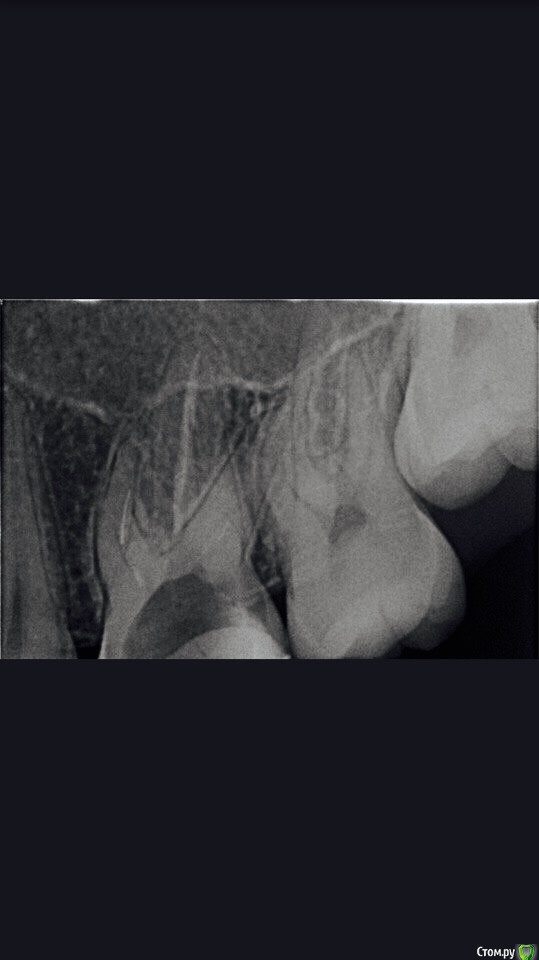

DmitrySH Опубликовано 19 января, 2017 Поделиться Опубликовано 19 января, 2017 Он в МБ2 похоже. Просвет МБ канала вполне визуализируется. В дистальном там не кончик файла? Ссылка на комментарий

Kolchanov Опубликовано 19 января, 2017 Поделиться Опубликовано 19 января, 2017 (изменено) Из мб2 я бы не стал доставать. Велик риск протереть корешок. Потом там часто такой зверский изгиб и, если это титан, то он там заклинен нормально. Изменено 19 января, 2017 пользователем Kolchanov Ссылка на комментарий